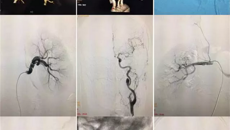

2017年6月15日-17日,由一附院牵头的“广西中医药发展联合体共建推进会”在南宁召开,全区219家医疗单位参与共建。此次会议以“共建共享、创新创业”为宗旨,将整合共建医院的医疗资源,上下联动,让基层百姓也能享受到大医院的优质医疗资源。 就在联合体共建推进会前一周,河池市中医医院推荐了一名“肾动脉狭窄”病人,经与一附院介入科罗耀昌主任沟通,联系病人收住我院外五科。病人是35岁...06.192017